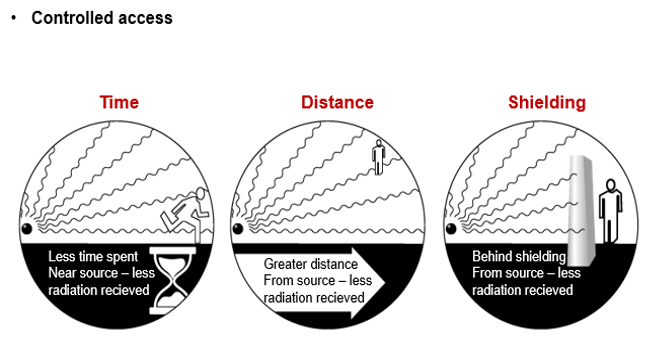

Personnel Protection

Consideration needs to be made to the exposure for operators during CT fluoroscopy. The radiation exposure to personnel can be substantial and equal to patient exposures in fluoroscopy during cardiac catheterization and interventional radiology so protection must be used. The 3 Cardinal Principles of Radiation Protection should be used: Time, Distance and Shielding.

The most significant area of radiation exposure to the radiologist is the hands that will be close to the scan plane during image acquisition while manipulating the needle under real-time imaging. This should be measured using a thermoluminescent dosimeter disc or ring. The absorbed dose to the hands in the direct beam is approximately 1.1 mGy per second. Other organs at risk from a radiation exposure perspective include the thyroid and lens of the eye. Departments will usually have a radiation safety threshold for staff on a per annum basis. Deterministic and stochastic effects could be developed if the radiation exposure exceeds 500 millisieverts per year and 50 mSv per year, respectively.

Shielding

Most traditional shielding, such as lead aprons or pieces of lead, can be used during scanning if no interference will occur in the scan. Lead aprons and thyroid collars are usually used for CT personnel when they must remain in the room during the exposures. It is important to use wrap-around aprons in this instance due to the presence of scatter radiation that comes from the patient.

Thick plated glass in the viewing windows and walls, designed to prevent radiation striking the walls from exiting the room, helps to prevent exposures to CT personnel as well as the public outside the room.

Shielding to protect specific radiosensitive organs in the body lying close to the primary x-ray beam can be used in CT. This includes areas such as breast tissue, thyroid or eye lens. Using Bismuth shielding (non-lead) when appropriate can result in the reduction of the dose deposited into the patient. It is important to remember that this shielding should be used only after the patient has had the CT radiograph (or scout image) completed as this could increase the selection of the automated mA value.